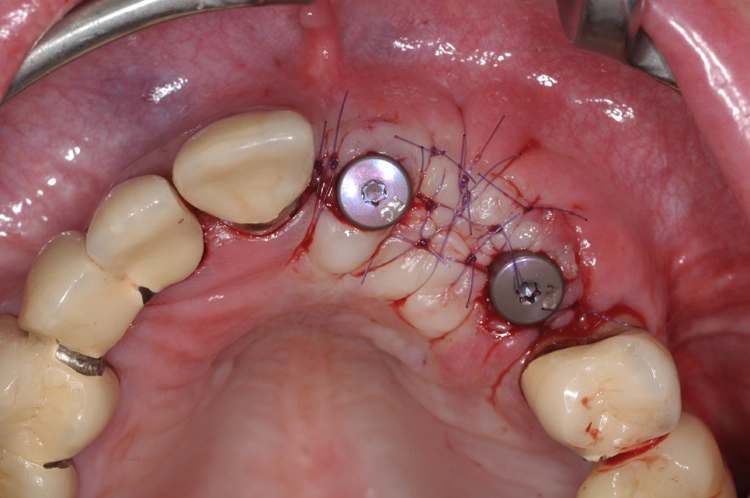

Die Abbildungen 11 und 12 dokumentieren das augmentative Relining, das zum Schutz vor Resorption und zur Konturaugmentation dienen soll. Dabei wurde eine Schicht bovines Knochenersatzmaterial (Straumann® XenoGraft) direkt auf den neu aufgebauten Knochen aufgetragen und mit Hilfe einer Kollagenmembran (Jason® membrane, Straumann) konturiert und vernäht. Damit legt man dem darunterliegenden neu aufgebauten Knochen einen Schutzpanzer an, der ihn einmal mehr vor Resorption schützt und die weitere Regeneration begünstigt.

Diese Form der Überaugmentation gibt dem Behandler nicht nur eine Möglichkeit an die Hand, die Konturen noch einmal zu justieren. Darüber hinaus treten erfahrungsgemäß im Rahmen der Implantatfreilegung auch weniger Weichgewebedefizite auf, die dann später durch entsprechende Transplantate wieder ausgeglichen werden müssten. Gerade im Frontzahnbereich ist eine möglichst große Volumenstabilität für das ästhetische Ergebnis von großer Bedeutung.